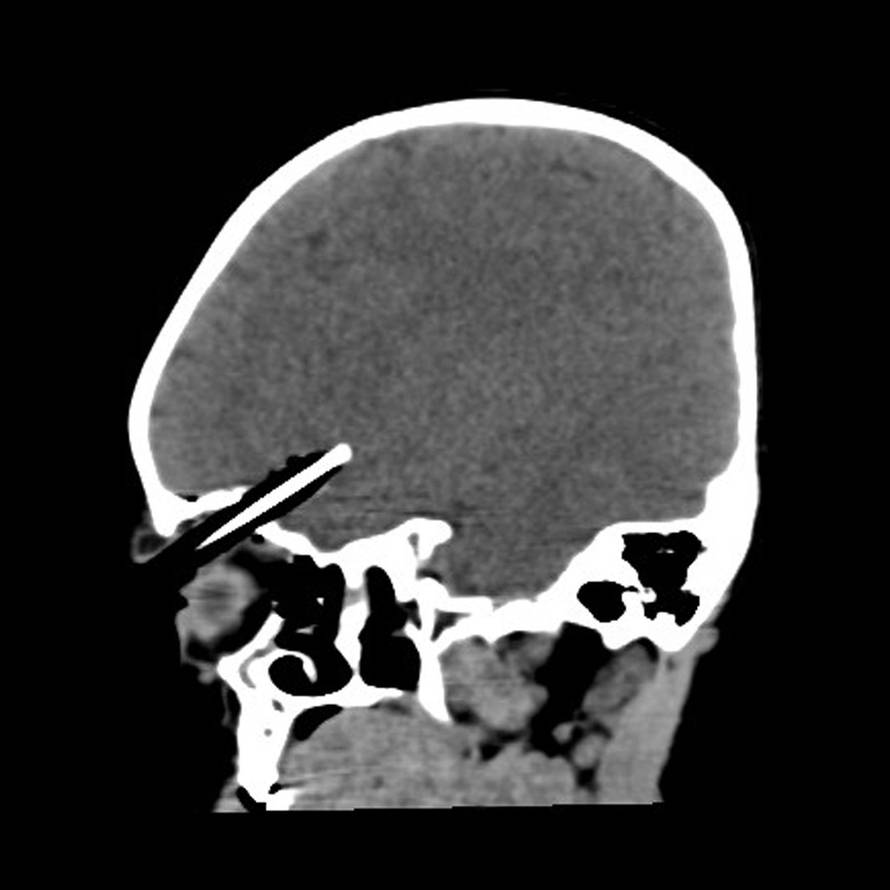

Velika Britanija: Curica je trčala u susjednu sobu da bi roditeljima pokazala svoju sliku. Spotaknula se i olovka joj se zabila u mozak. Operirali su je četiri sata